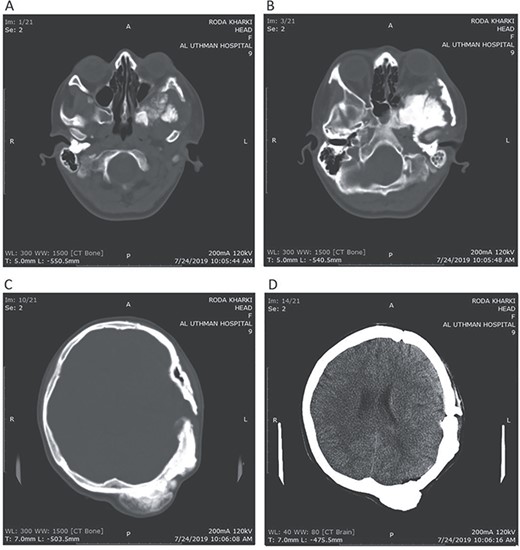

CT head bone window (A–C). A. Invasion of the frontal bone. B. Invasion of the orbit. C. Invasion of the parietal bone. D. Invasion of the sphenoid, temporal and parietal bones.

A 17-year-old female presented with a history of osteosarcoma that was confirmed after undergoing a surgery to remove an enlarging bone tumor in the left temporal region 2 years ago. She later got pregnant and delivered her child but never got back for a checkup until she was admitted to our hospital with a severe and unresponsive to medication headache that progressed over the course of 6 months and blurred vision that progressed to complete left-sided vision loss. Physical examination revealed a tough and mobile yet fixed at the base 7-cm mass towards the left of the frontal bone. Many more masses were revealed in the left side of the skull including the anterior cranial fossa, orbit, base of the skull and the left part of the occipital region where the previous procedure was performed (Fig. 1). These masses had been increasing in size probably under the influence of pregnancy hormones causing pain that radiated along the orbital and maxillary branches of the left trigeminal nerve. Physical examination and past medical history were otherwise unremarkable. Laboratory tests were all normal, and her family history was negative. Staging studies showed no evidence of distant metastatic disease in the chest, the abdomen and the pelvis. CT scan of the skull revealed a bone-forming non-lytic lesion accompanied by periosteal reaction. This lesion bulges to the outside towards the scalp spreading into both the soft tissues and the inside of the entire left side of the skull with a sunburst-pattern (Figs 2 and 3). Its rims are unsymmetrical and pointy, and it bulges into the left orbit outside the muscles causing exophthalmos with a semi-complete proptosis of the eyeball out of the orbit (Figs 2 and 3). This lesion applies pressure to the left frontal and temporal lobes causing mild edema in both these lobes without invading the brain tissue. This edema in turn applies pressure to the left lateral ventricles (minor shift of the elements of the midline to the right side can be seen on CT) (Fig. 4). Due to the tumor’s wide spread, the surgical procedure was performed in two stages (approximately 6-hour-long each). In the first stage, the bone mass was removed through a procedure of wide skull approach including the frontal, temporal and parietal bones and a removal of the invading part of the temporal muscle. Moreover, the lateral wall and roof of the left orbit were removed, the left optic nerve was dissected free and part of the meninges was removed and replaced with an autogenic patch from the fascia lata. Then, the bone loss was compensated for by using bone cement Synicem VTP (poly methyl methacrylate and Barium sulfate), and the orbit was rebuilt; the eyeball was placed back with noticeable decline of the exophthalmos. In the second stage, a complementary left parietal occipital incision of the previous approach was performed 3 weeks later; the remaining of the frontal and occipital bones was removed, and a partial mastoid surgery was done. Furthermore, the cavernous sinus were revealed and found to be not invaded. Later on, the normal skull shape was restored using the same cement. The histopathology of the lesion revealed proliferation of neoplastic chondroblasts, osteoblasts and spindle-shaped cells. The features are consistent with low-grade chondroblastic osteosarcoma (Fig. 5). The patient did not need ICU admission. She recovered well 3 days after the surgery and was discharged with no deficits. A CT scan that was performed post-operatively revealed that the masses were successfully excised (Figs 6 and 7). At the last follow-up 1 month post-operation, the patient was scheduled to undergo a course of radiotherapy, 60 Gy of radiotherapy in 30 fractions over 4 weeks without chemotherapy, as it is not recommended with low-grade osteosarcoma.